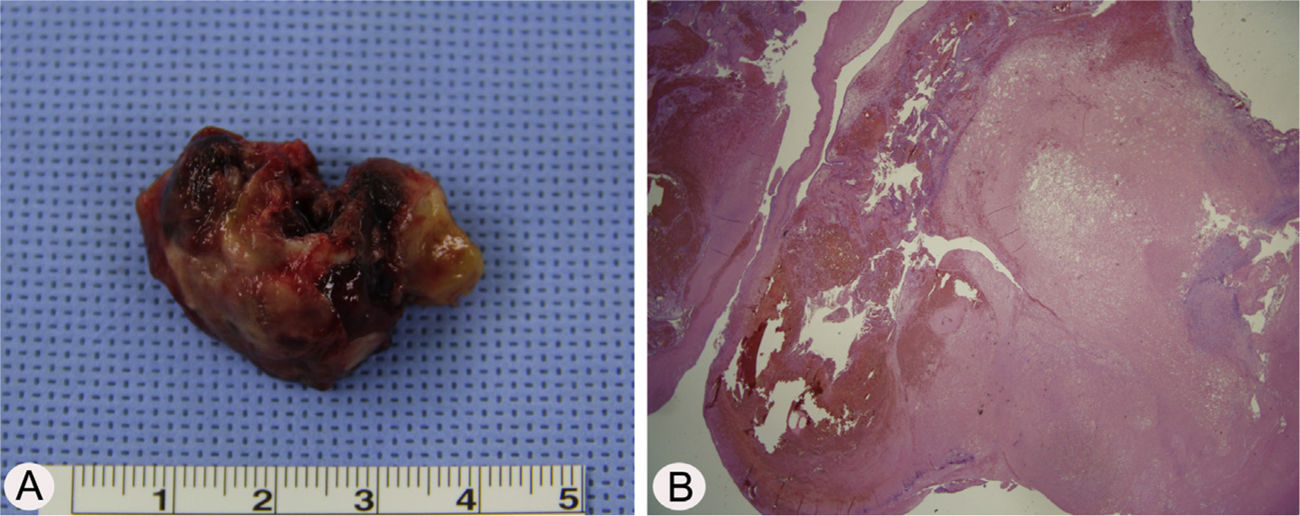

Case reportA 17-year-old male was referred to our outpatient clinic because of recurrent epistaxis after left nasal polypectomy. He had undergone nasal polypectomy due to nasal congestion at a local clinic 10 days ago. He had neither other symptoms nor any medical history. There was no history of trauma and no sign of allergy. The endoscopic examination revealed bulging of lateral nasal wall and bleeding due to left maxillary sinus mass (Fig. 1A). A Computed Tomography (CT) scan of the paranasal sinuses showed heterogenous enhancing mass in left maxillary sinus without adjacent bony involvement (Fig. 1B and C). On Magnetic Resonance Imaging (MRI), the mass expanding left maxillary sinus had mixed high signal intensity on T1-weighted images (T1WIs) and heterogenous high signal intensity on T2-weighted images (T2WIs) with an avid enhancement (Fig. 1D–F). Considering the location of tumor, surgical access was gained via Caldwell-Luc approach under general anesthesia because transnasal endoscopic sinus surgery had high risk of bleeding. The mass was originated from medial wall and partial superior wall of left maxillary sinus (Fig. 2A and B). The base of the lesion including the healthy mucosa around it was successfully removed with harmonic scalpel and microdebrider under direct visualization using a nasal endoscope and cauterized using suction cautery for prevention of recurrence (Fig. 3A). Histopathologic examination showed variable sized and irregular shaped vascular spaces with thrombus, consistent with arteriovenous malformation (Fig. 3B). Postoperative course was uneventful and he was discharged five days after surgery. Endoscopic examinations and CT performed 3 months postoperatively showed no evidence of recurrence.

Preoperative endoscopic and radiologic findings. Nasal endoscopy (A) shows bulging of left Lateral Nasal Wall (LNW). Axial (B) and coronal (B) computed tomographic images shows heterogenous enhancing mass in left maxillary sinus without adjacent bony involvement. The mass shows mixed high signal intensity on T1 axial (D), avid enhancement on postcontrast T1 axial (E), and heterogenous high signal intensity on T2 coronal (F) magnetic resonance images. S, nasal septum.